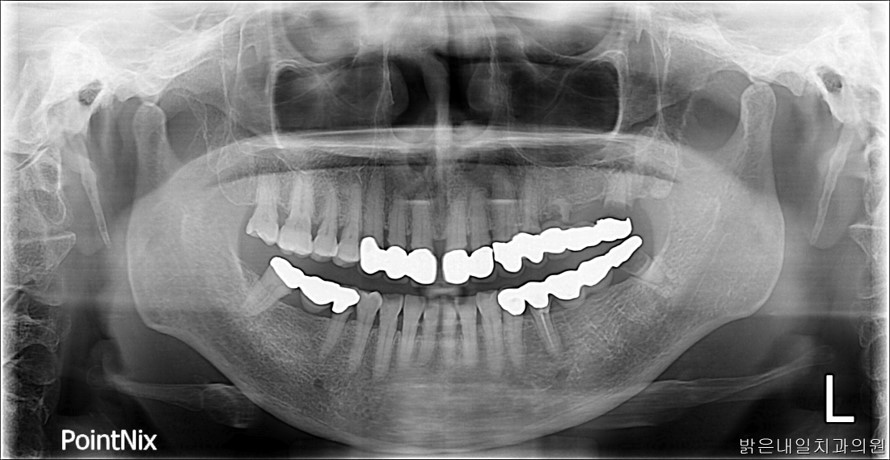

치료전후사진